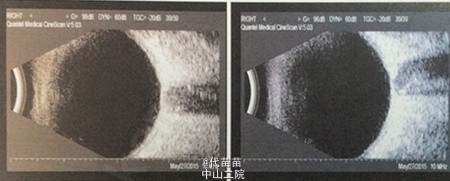

视力:VOD:0.5 ,VOS:无光感,IOP:OD7 mmHg,OS21 mmHg,中央前房深度3CT,周边1/3CT,虹膜未见萎缩,瞳孔3×3mm,人晶在位,眼底C/D=0.2。左眼轻充血,角膜清,中央前房深度2CT、周边裂隙状,瞳孔大,直径约4mm,晶体混,眼底窥不入。 右眼房角开;左眼全周房角关闭。 右眼角膜内皮正常;左眼角膜内皮测不出 UBM:右眼人工晶体眼 左眼房角关闭

诊断:1.左眼继发性青光眼 2.左眼老年性白内障 3.右眼人工晶体眼 手术:左眼白内障囊外摘除术+人工晶体一期置入术